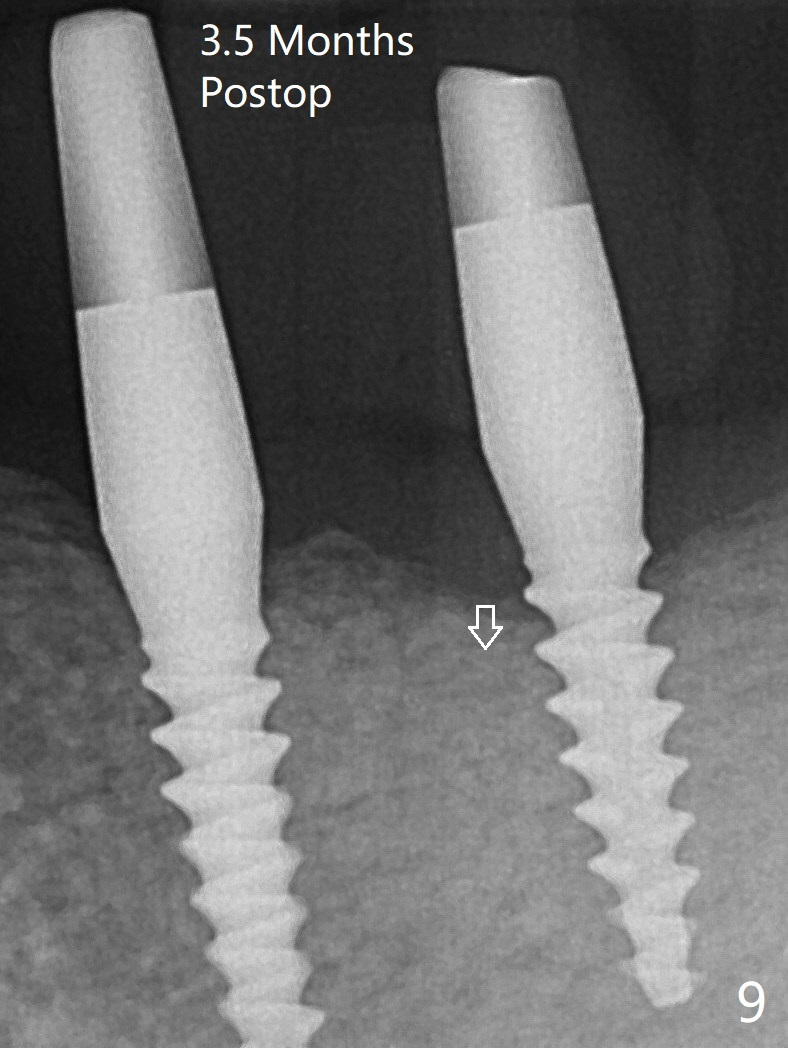

左下第一磨牙(#19)牙槽嵴狭窄,2.2毫米钻头完成导板钻洞后,舌侧骨板开始破裂(图一:<),打消牙槽嵴劈开术念头,放置2.5x8.5毫米一段式植体(图二(8.5毫米是最短植体)),好像离下齿槽神经管还有一定距离,适当植入深些(图四:箭头,15Ncm)。右下中切牙缺牙区牙槽嵴也十分狭窄(图四),最后不得不徒手植入2x8.5毫米植体(图五,六,25Ncm)。如果按设计植入2x12毫米植体,颊侧,或者舌侧骨板更容易穿孔。术后3.5月牙槽嵴下降(图七:箭头),可能术中那里压力太大,今后牙槽嵴钻洞要大。24号牙根尖阴影(图七),完成根管治疗(图八)。19牙位牙槽嵴吸收也严重(图九)。其实术后4个月19牙位牙槽嵴吸收并不严重(图十一)。